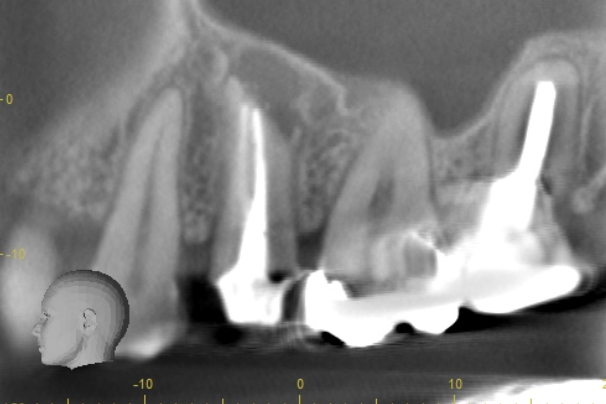

| 根の中にお薬を充填した後のCT画像。やはり根の先に黒い影があるのがわかります。 |

| 根の先の黒い影は消失しました。 | 術後6ヶ月のCT画像です。こちらでも、根の先に黒い影は見当たらないです。 |

患歯を見極めるためと、状態の悪さをみるため、CTを撮影しました。治療前では上顎洞への大きな炎症が見られます。また、上顎洞底線も無くなっています。また左上の前から4番目の歯の根尖周囲にも透過像が見られます。5番目の歯に関しては根尖が鋭利になっており、根尖性歯周炎によって吸収されたことがわかります。ですので、まず第一の患歯は5番目の歯であるとしました。

治療後3ヶ月経つと上顎洞への炎症も無くなっています。また、上顎洞底線もきれいにみえます。4番目の歯の根尖周囲の透過像もなくなりました。5番目の根尖にまだ透過像がありますが、臨床的症状がないことから、治癒傾向にあるものと判断しました。